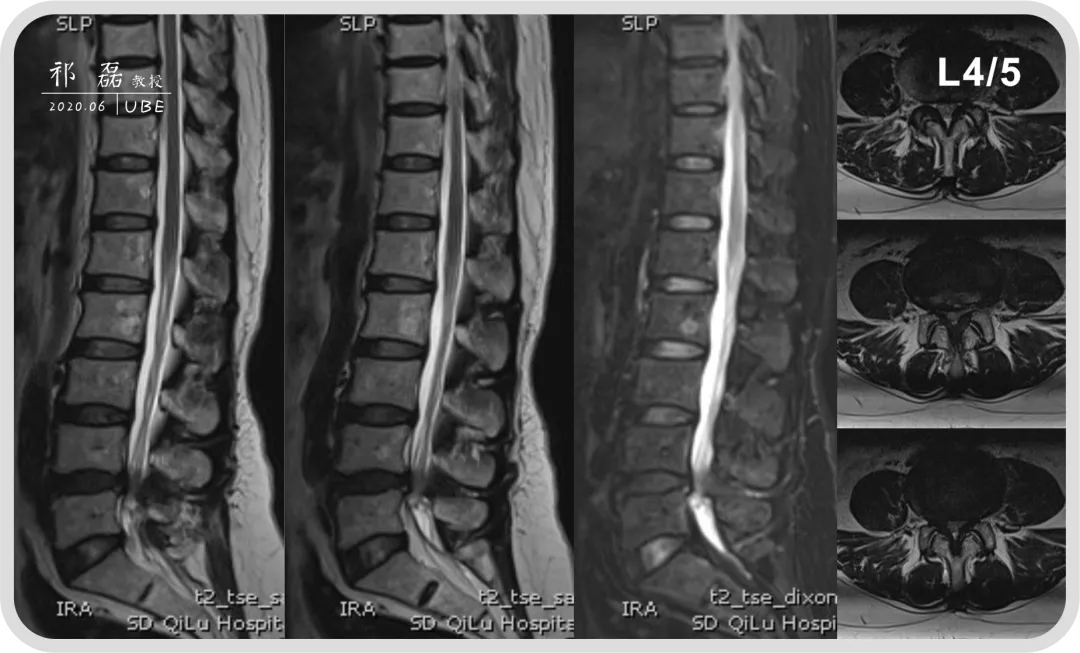

患者:吴某,女,53岁,腰痛及双下肢疼痛麻木5年余,加重1月余,间歇性跛行约200米。于近日入我院查体,下腰椎棘突及椎旁肌深压痛,双下肢感觉运动正常。双侧直腿抬高试验(-),双侧踝反射(-),入院诊断为:腰椎管狭窄症。

图3:腰椎MRI